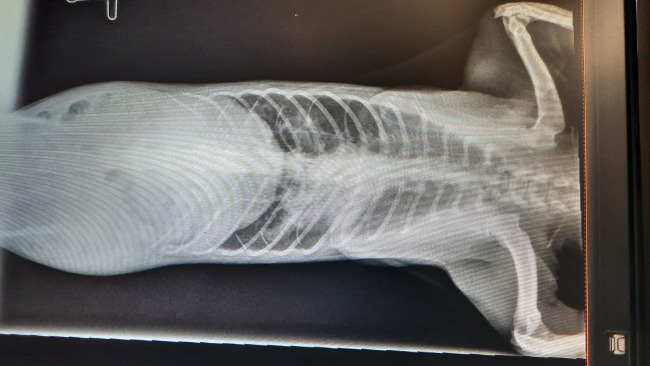

Już na pierwszy rzut oka widać było zły stan sierści, problemy z zębami i ogólne wyniszczenie organizmu. Zleciliśmy badania RTG, USG, badania krwi w profilu rozszerzonym, testy FiV i FeLV.

Badania wykazały stare zmiany pozapalne w płucach, Piecyk ma również problemy z trzustką, wymaga specjalistycznego karmienia karmą gastrointestinal, musi przyjmować suplemenstację oraz preparat ScanoMune na odporność. Wykryto również liczne wszoły... Ogólnie dobrze NIE JEST !